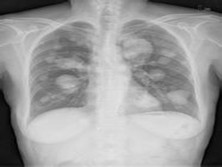

肺转移瘤是指原发于其他部位的恶性肿瘤经血液或淋巴液转移到肺脏组织。死于恶性肿瘤的患者中,20%~30%有肺转移。肺转移发生的时间长短不一,少数肺转移瘤比原发肿瘤更早发现。原发恶性肿瘤多来自乳腺、骨骼、消化道和泌尿生殖系统。肺转移瘤多为两肺多发性病灶,大小不一,密度均匀。目前尚无有效的治疗方法,肺内单个转移病灶可考虑外科... [详情]

• 应该做哪些检查项目呢?胸部MRI、胸部CT、X线平片

A: 肺转移瘤最常见的CT表现有多发结节影、磨玻璃样结节、空洞性病变、淋巴结肿大等。...